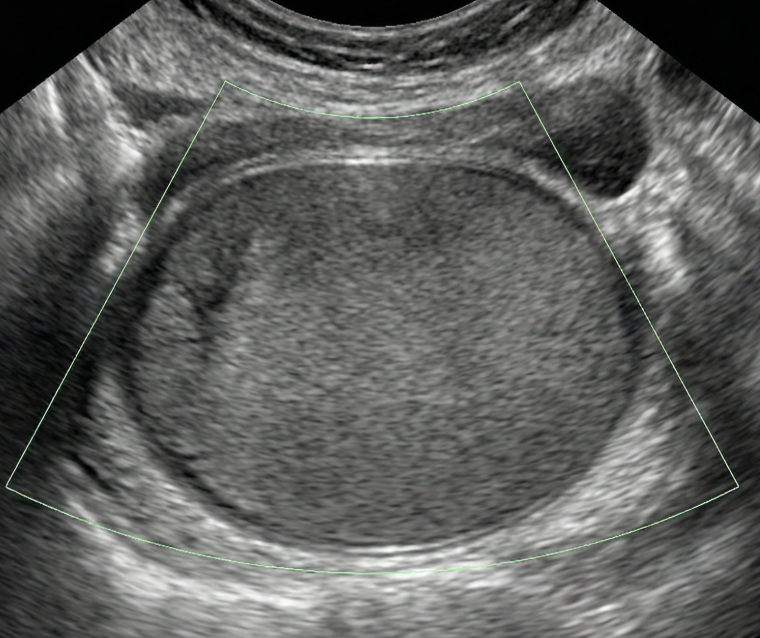

As regras simples do IOTA são um sistema de classificação baseado em características ultrassonográficas específicas que ajudam a distinguir massas anexiais benignas de malignas.